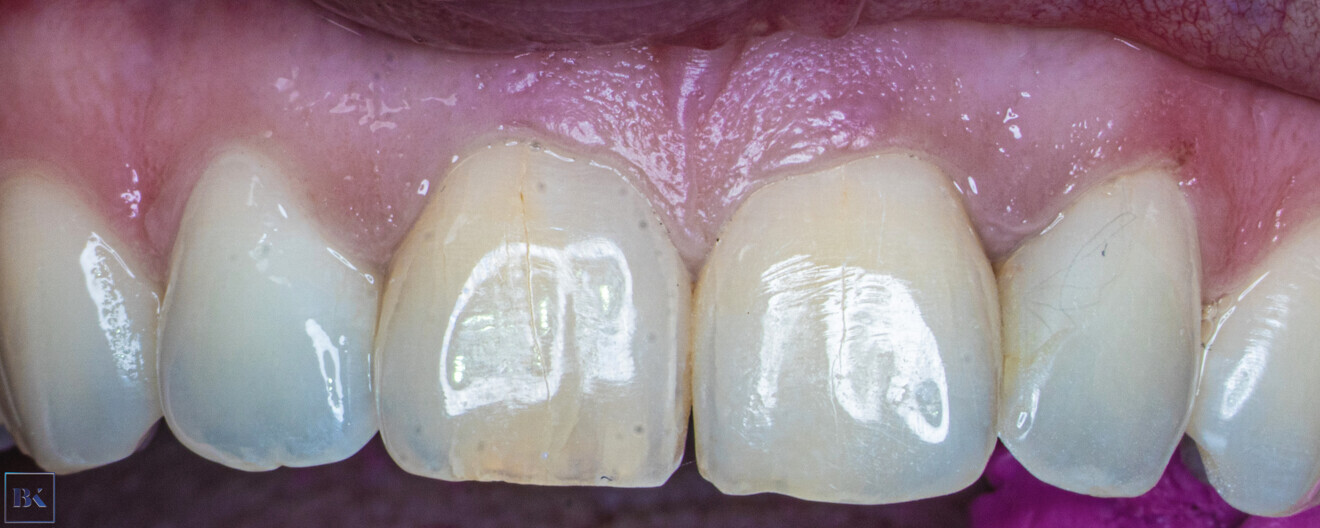

A 36-year-old female patient came to the dental office with discoloration and pain of the maxillary right first incisor (Fig. 1). In the medical history taking, she reported a trauma approximately 15 years earlier. During the radiographic examination in the office of her general dentist, PCO was revealed. She was referred for a CBCT scan and endodontic treatment.

Fig. 1: Intra-oral view of the initial situation. Visible discoloration of the right central incisor.